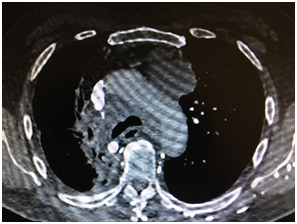

C’est le scanner thoracique avec injection d’iode qui oriente le diagnostic : nodule, trouble de la ventilation, ganglions etc…

Un scanner thoraco-abdominal injecté,